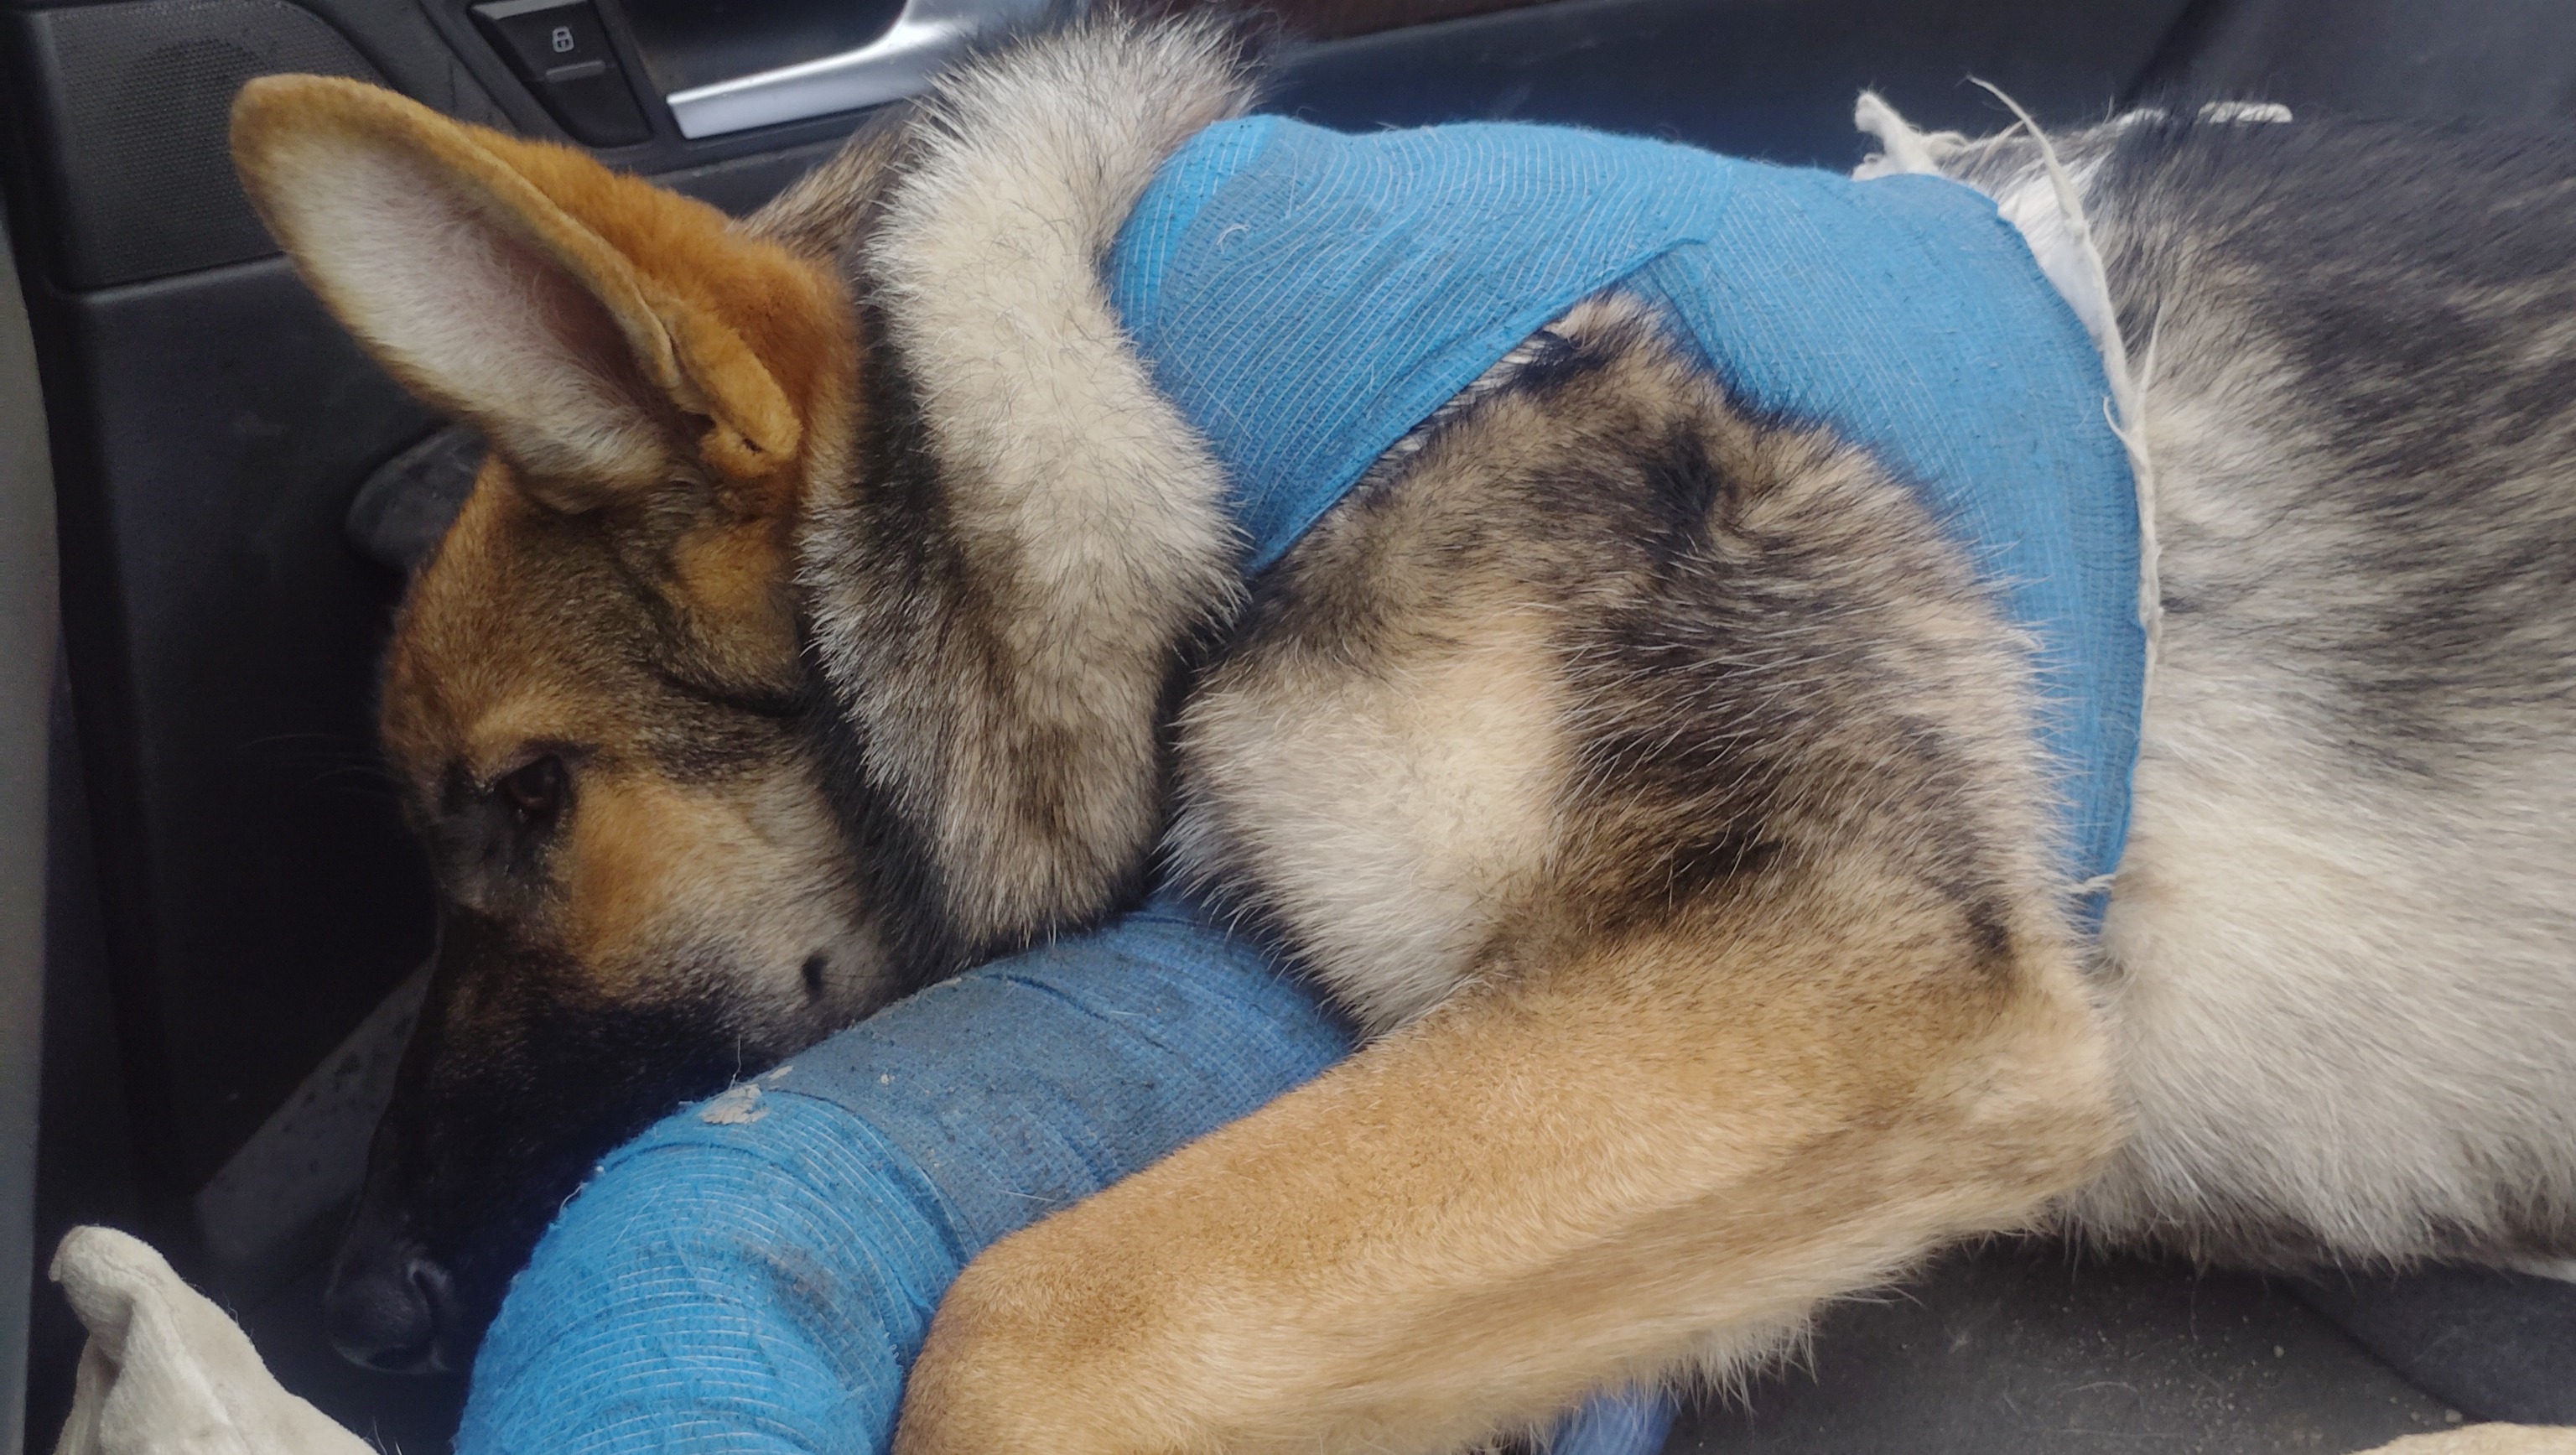

- So I'm sure by now Samuels legs started healing and I haven't been able to keep him from walking on it and it looks like he can't move his leg instead he's throwing it in front of him and pivoting off it which I know is hurting him. The vet said their going to have to rebreak his leg then plate it back together, I've managed to raise another $450 so now we're only about $550, that's hoping they will rebreak it included in the previous estimate, Well cross that bridge when it comes.

- So these are Samuels X-rays. They show that his front right leg has a break in the upper part of the bone near his shoulder. The veterinarian said he most likely has his weight planted on that leg at the point of impact. He also had damage and bruising to his lungs causing small lesions where air was escaping into his chest cavity pushing his heart up and forward. They said this would heal on its own but would be uncomfortable for him during the process. Thank you to everybody who's donated and shown love and support for my pup. Time is definetly a factor here so I'd like to ask everybody to share this posting and know that your donations are going to a noble cause and will impact our lives forever. You are appreciated.

- Trying to think on my feet here, I'm 100% against amputation, especially for GSDs unless every other option is exhausted. It looks like the most affordable way to get him the specialized surgery he needs is to drive down to Mexico and have them do the surgery there. Mexico has. Some of the worlds best doctors and veterinarians in the world it's just a more affordable option to those that may be down on their luck. So we're looking at a new goal of 3500 with 1047 already met. Help us save Sammy's leg by donating today! All money collected on Samuels behalf will go toward gas to get him to Mexico and the surgery. They will be keeping him overnight at the animal hospital, I'll be sleeping either in the lobby or in the car with Sam's brother Tiny, then when he gets released from the vets we'll be coming back. Apparently this is fairly common practice for the vets, having Americans bring their pets across the border for medical care and they said they will give us medical papers for Sammy and that's all we should need to get back in to the U.S. plus if that feels sketchy they offer a pet express pickup to and from the vets for $18 I believe. So this looks like the plan as of now. Sammy's in pain and if it means he will heal and keep his leg and be done with the pain, I don't mind the nine hour drive. If I had the money this would have been taken care of immediately unfortunately due to a series of events Im unable to afford it myself. That's why I'm panhandling on the internet for donations for Sam. A little embarrassing but for a righteous cause so that's just the price I pay.

Hello, I'm fundraising to get my 7 month old German shepherd pup the surgery he needs to save his front leg.

It's important to me because these guys are family now, my 7 month old is hurt.

All the proceeds from this fundraiser will go directly toward his surgery and pain medications for him.

I would like to ask for your help getting this poor little guy back on his feet, He's just a baby. He doesn't deserve suffering thru all this pain. Getting hit by a car at just 7 months old, that's crazy.

Meet Samuel, an amazing German shepherd puppy that would melt anybodys heart. I rescued Sammy when he was just 3 months old, I had answered an add on Facebook about someone needing an unexpected liter of German Shepherds gone asap. I drove around 3 hours to go pick him up and when I got there and saw Samuel and his brothers I knew I had to take them out of that situation. I asked the person how many were available. They said someone was coming to take 2 of them and there was three left including Samuel, I said I'll take three and I loaded them up in the car and pulled off. Samuel was a bit bigger then his brothers but not by much, all three of them were literally starving to death and practically skin and bones. I noticed Samuel had a big chunk of his ear missing and was curious about it so I messaged the person I got him from and asked what had happened, I also wanted some info on there shots, because from the moment they got in the car they had diarrhea and were pooping and vomiting everywhere, and all three of them huddled together under the back of the driver seat in the car nearly the entire ride home. The owner told me that Sammy's mom had bit Samuels ear off when he went in her food bowl and that none of the dogs had their shots yet. I started worrying that these poor guys had parvo or something. Along the way I made a few put stops to clean up the poop and vomit and try to get these guys fed and hydrated, we eventually made it back home and I managed luring these guys out of the car by sitting there talking to them for around a half hour or so and some puppy treats. These pups weren't acting how you would expect your typical pups to act, playfull, energetic, happy or anything. These guys seemed terrified. I got them inside and into a warm bath to clean them up. I didn't want to freak them out so I put some food and water out and sat back and gave them their space. I figured it might take them a little while to adjust to their new environment and such. They started warming up to me the next day altho the three seemed to all have some sort of separation anxiety going on or something. My goal at this point was to gain their trust in me so, yes it was super cuddle time. After a few days they were jumping all over me and showering me with kisses every chance they got... After about a week their stools started becoming normal which was a huge relief. They picked up weight quick and almost seem to pack on the pounds daily. As much as I fell in love with all three of them I knew it was to much to handle by myself so I gave crash to one of my friends because he seemed like he needed a bit more one on one attention then the other two so it seemed like the best thing to do. Fast forward 4 months and these guys are with me everywhere I go until about 4 or 5 days ago when I had to run an errand and had to leave them at home. So I went to take care of it and when I got back Tiny was inside freaking out, and I was calling Samuel but he wasn't coming and I knew something was wrong. I started looking around inside but he wasn't there so I went outside and started calling for him and noticed a piece of paper on my door. It was from animal control, it said that they had been called out because the dogs had gotten out and when they arrived they saw Samuel lying in the middle of the street and that he had been hit by a car. And gave me a phone number to call, I called and they gave me the address where I could see Sam, I rushed down there and wanted to see my dog and they told me it would be 300 dollars to get him out, and the animal control guy who scooped him up told me he had broken bones and internal bleeding so I'm freaking out and I asked them if they got him any medical treatment and the guy said he put some pain pills in some food and left it there for Sam. I wanted to see Sam immediately I told them and the guy brought me back to where Sam was, locked in a cage lying on the ground in pain crying and nobody even comforting him. My eyes teared up and I called out to him telling him it would be ok. Nothing moved on him except his tail started wagging when he heard my voice.. this sent me over the edge, I had to come up with 300 bucks right now! I was so mad and hurt that they left him in there like that, it literally was like someone punched me in my gut. Three hours since he had been hit and stuck in that cage in was able to piece together enough money to bail my injured pup out and get him to an emergency vets office. I'm forever grateful to VEG in San jose for doing everything they could to take care of my pup even tho I had no money and the credit places they worked with wouldn't help with the 7500 estimate they had written up for Sammy's care plan. My heart was broken but I kept reaching out to more and more places but ran into dead end after dead end. Maybe the vets sensed my level of heartbreak and desperation because they didn't stop taking care of Sam even when they knew I had no way to pay for the medical aid. They gave me pain pills, anti inflammatory pills and anxiety pills to take home for him and even ran some X-rays so I knew what it was he still needed, hthe x-rays showed Sammy had bruised lungs and that air was getting into his chest and pushing his heart upward and that his right front leg was broken clear thru the bone. My heart sank and as much as I tried holding it in but tears started rolling down my face. They said that he would need orthopedic surgery soon or he would lose the use of it and need it amputated. Then they asked if I wanted to amputate his arm. I knew he was in pain and amputation could end that pain for him but I had to make the hard decision to not amputate his arm until I exhausted every single resource or means of generating enough money for the needed surgery to save his arm first. Some people say that he would live just as happy of a life with three legs as he would four, but Ive had a German shepherd with bad hips before and I knew that if I didn't fight with everything I had and let him lose him front leg that if he were to get bad hips later on in life only having one front arm that he would suffer just walking to go to the bathroom. It was hard decision but I made the decision I felt was best for him in the long run. I hate that he's in pain Everytime he tries to get up and move around and he keeps trying to and bumping his arm into things or getting it caught on something and crying everytime he does. I'm trying to keep him as relaxed as possible but it's been a challenge since he's used to multiple trips to the park a day and racing with his brother when I throw the ball to see who can get to it first and try to race back to me before the other grabs his tail causing him to do a somersault tuck and roll type deal or getting tackled by the other in the process. He's had such an active lifestyle that laying there all day just doesn't calculate to him... Im in a desperate situation at this point, He needs this surgery to save his arm to ensure him the best possible chance at a happy, healthy life and if I can't raise the money in time then all his suffering will have been for nothing. I'm to far in to turn back now and I need to keep pushing forward in my efforts to save his arm. He deserves nothing but the best and he's worth every blessing he gets. I love these two guys very much and there isn't anything I wouldn't do for them. Please if you can help Sam I would be forever grateful for it. Anything helps even reposting this gofund.me fundraiser for him. These guys are like my babies and my best friends, please help me help them. Thank you